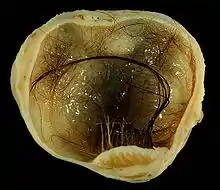

Teratocarcinoma (teratomas malignos)

Teratomas são crescimentos descontrolados de células, que geralmente são compostos de vários tecidos, como cabelos, músculos e ossos, ocorrendo com maior frequência nos ovários (mulheres) e nos testículos (homens). Quando esses teratomas são malignos, eles são chamados de teratocarcinomas, sendo considerados um tipo de câncer.[61]

Nesse tipo de câncer, o tumor não é causado por uma mutação genética, mas sim pelo ambiente externo da célula. Através de experimentos, sendo o mais famoso realizado com camundongos, observou-se que se uma massa de células é colocada no interior de um blastocisto de camundongo, ela vai se integrar ao blastocisto, perder sua malignidade e se dividir normalmente; caso contrário, se ela for colocada em uma outra região, isso pode levar à formação do teratocarcinoma, tornando-se um tumor maligno.[61]